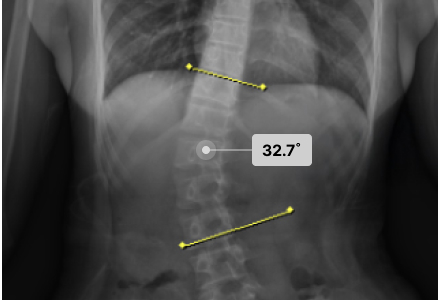

척추측만으로 휘어진 허리 때문에 일상조차 버거웠던 환자분들이

두드림의 교정치료를 통해 뚜렷한 변화와 회복을 경험하고 있습니다.

· 각 치료사례는 환자분들에게 사전 동의를 받아 동일 조건에서 촬영된 이미지입니다.

· 개인에 따라 치료 결과가 달라질 수 있으니 의료진과 충분한 상담 후 치료를 진행하시길 권장드립니다.